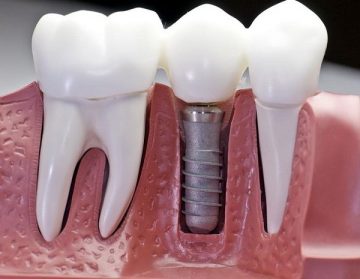

Имплантат – конструкция, вживляемая в костную ткань челюсти, на которой держится искусственный зуб. Имплантаты бывают внутрикостные, поднадкостничные, чрезкостные.

Имплантаты с качественной коронкой успешно имитируют родные зубы и часто используются в современной стоматологии.

Самым современным способом восстановить безвозвратно утраченный зуб считается имплантация. При этом корень заменяется особой формы стержнем, вживляемым прямо в кость челюсти, а вместо коронковой части устанавливается на стержень искусственная коронка.